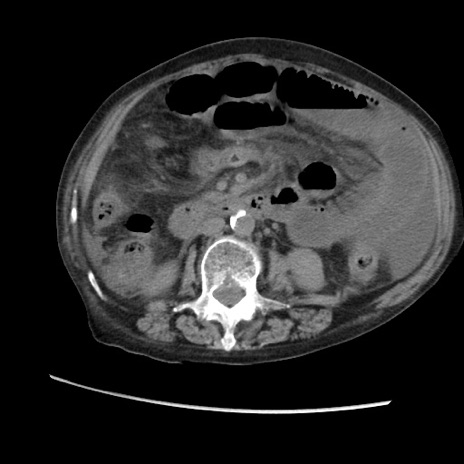

症例31(横断像)

【症例】80歳代 女性

【主訴】腹部膨満感

【現病歴】他院にて肝硬変にてフォロー中。1週間前から便秘、腹部膨満感、臍部腫瘤あり受診となる。

【既往歴】肝硬変

【身体所見】腹部膨隆あり、皮膚変化なし、疼痛なし。

【データ】WBC 4600、CRP 0.25